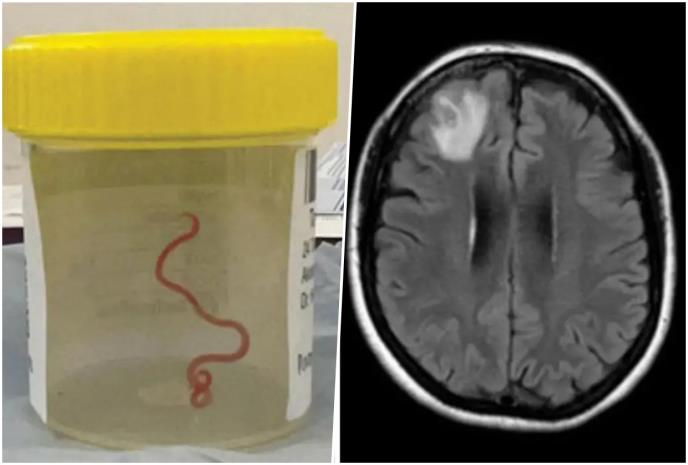

Do 2022. godine njeni simptomi su postali ozbiljni, počela je da zaboravlja i pada u depresiju. Lekari iz male lokalne bolnice uputili su je stručnijim kolegama u Kanberi gde je MRI (magnetna rezonanca mozga) otkrila neke abnormalnosti koje su zahtevale operaciju. Ono što su lekari pronašli u njenom mozgu iznenadilo je čak i njih - živog crva dugačkog 8 centimetara.

crvumozgu-copy.jpg

Foto: hospitalhealth.com.au